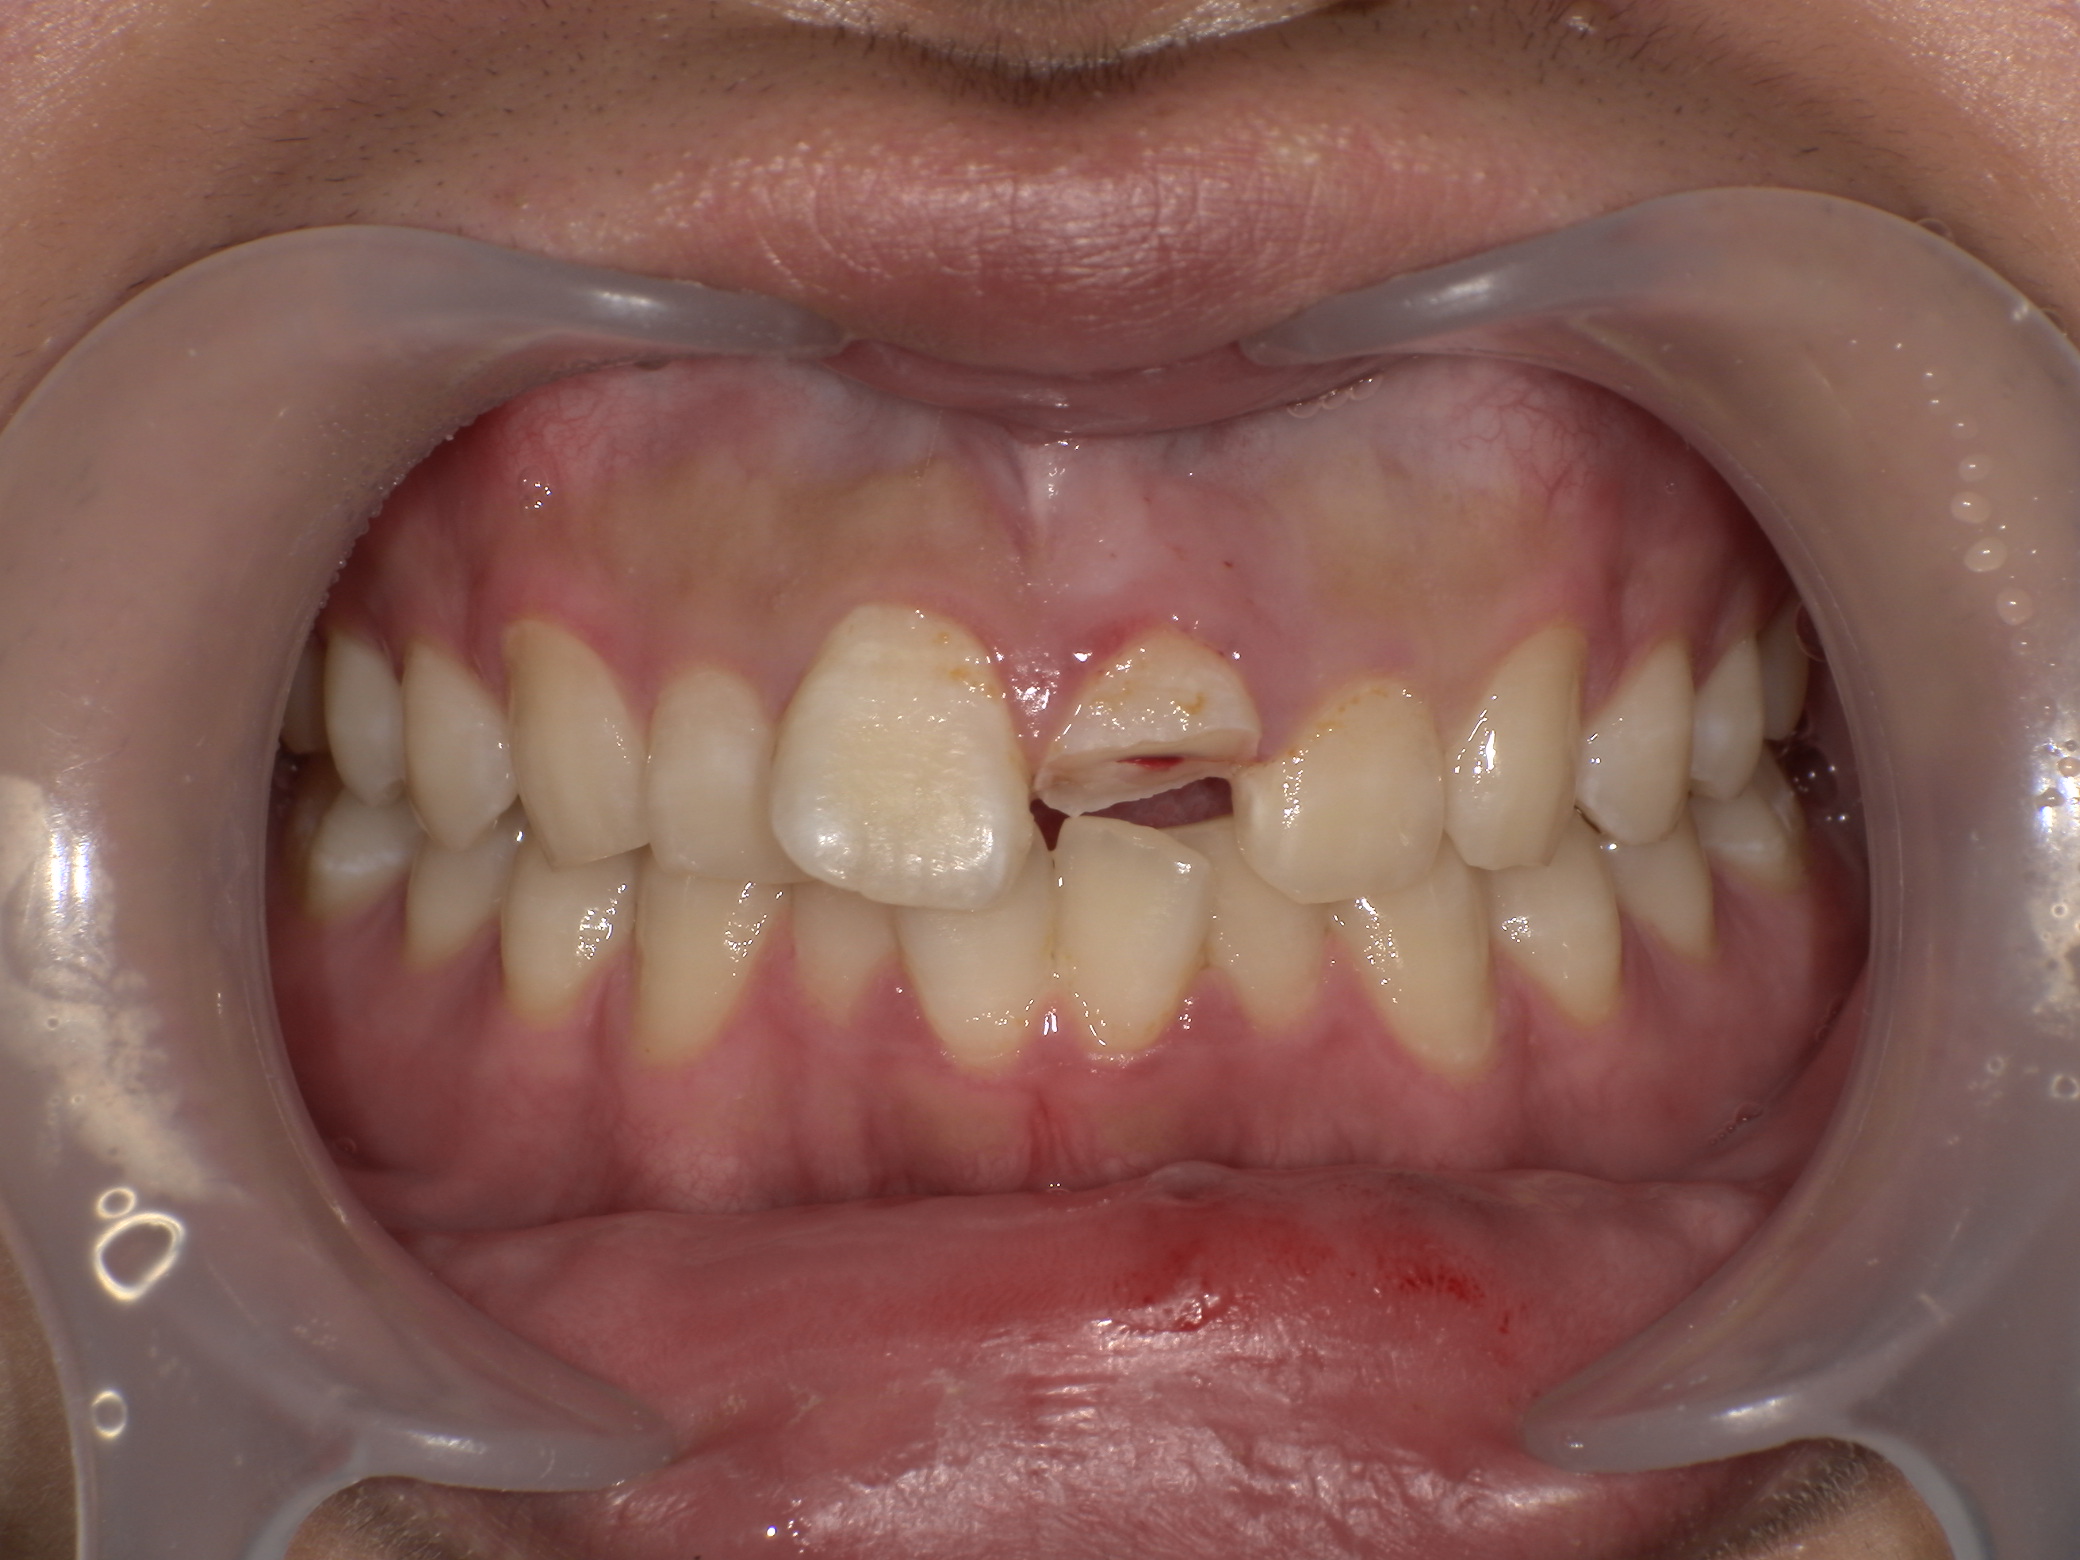

e-max(オールセラミックス)症例|ケガで前歯が折れた

2026/04/07 審美歯科